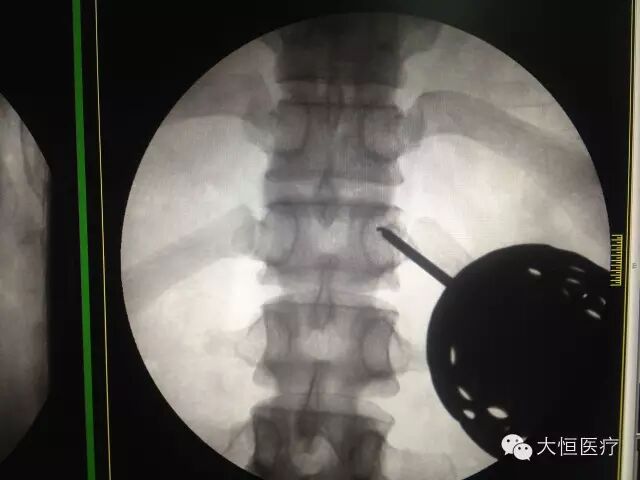

临床图像c臂怎么启动全智能型疼痛科/介入型C型臂_https://www.jmylbn.com_新闻资讯_第3张

临床图像

c臂怎么启动全智能型疼痛科/介入型C型臂_https://www.jmylbn.com_新闻资讯_第2张